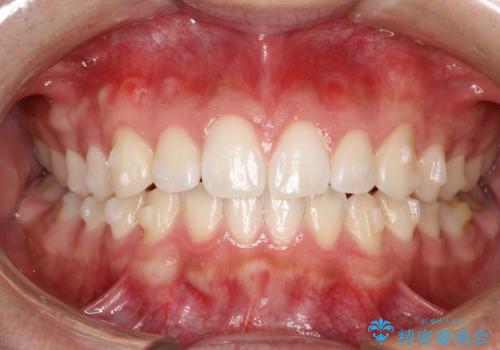

前歯の隙間がきになる インビザラインですきっ歯の治療

- 上の前歯の隙間を主訴に来院されました。

正中に隙間があり、かみ合わせが深い過蓋咬合という状態でした。

インビザラインにて矯正治療を行いました。

しっかり使っていただけたので、スムーズに治療を終了することができました。